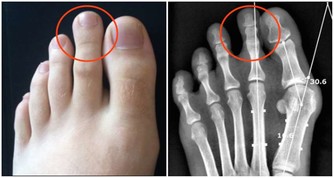

我們的手臂中含有多條動脈和靜脈。如果是深層的靜脈組織出現血凝塊,那麼會導致手臂皮膚發紅腫脹,還會伴有劇烈的疼痛感,這種病情在醫學上稱之為深靜脈血栓形成。

在某些情況下,手臂處的深靜脈血栓會分離出一部分隨血液流動,最終會進入肺部,誘發肺栓塞。

動脈栓塞是指血栓或血管中的異物阻礙了動脈血液流通,當栓塞到達手臂動脈時,

通常會引起手臂皮膚變色、手指冰冷異常,患者還會感覺上肢無力,或是直接喪失手臂的運動能力。